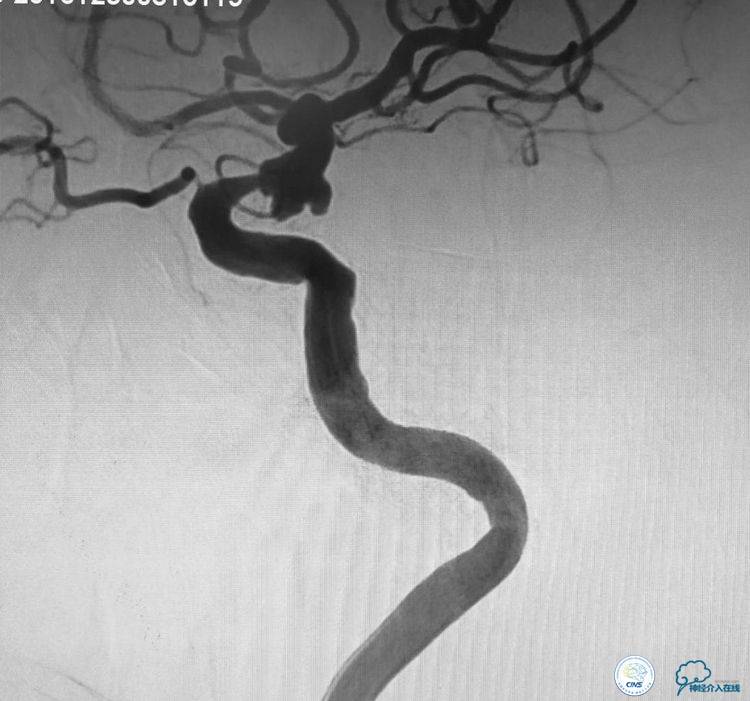

▼动脉瘤致密栓塞,血管狭窄改善,载瘤动脉通畅。

本例手术的特点和难点:髂动脉、主动脉、颈动脉迂曲,左侧颈动脉开口有狭窄。后交通动脉瘤呈宽颈分叶状,动脉瘤近端有一个约80一90%的狭窄。

治疗策略:采取支架辅助弹簧圈栓塞治疗动脉瘤。但由于动脉瘤近端的血管狭窄,如果不实施对狭窄血管的干预,支架释放后,很可能会导致支架打不开或者导致血管闭塞。因此首先对动脉瘤近端的狭窄血管进行球囊扩张,扩张的危险性就是有可能会导致动脉瘤的破裂。因此我们选用了超柔顺性的球囊。球囊扩张之后置入支架,由于动脉瘤呈分叶状,所以我们选择了双微导管支架辅助弹簧圈栓塞治疗这例动脉瘤,取得了良好效果。